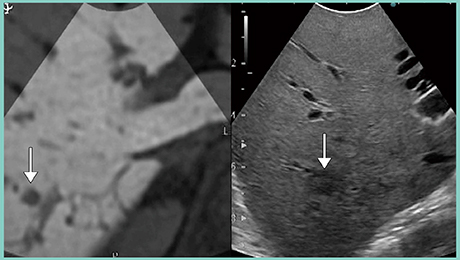

症例2は,大腸がん肝転移症例で,後上区(S7)に腫瘍があり,主要な血管をメルクマールにして超音波画像と造影MR画像の位置合わせを行った。RVSでは位置合わせに若干のコツが必要であるが,本症例ではS7の腫瘍が2つの画像で並列に同期表示できている(図3)。

図3 症例2:大腸がん肝転移症例(↓)(位置合わせ)